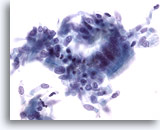

Figure 1

Bronchoalveolar lavage

Low magnification showing an admixture of epithelial cells and macrophages. 20x

Bronchoalveolar lavage

Low magnification showing an admixture of epithelial cells and macrophages. 20x

Figure 1

Bronchoalveolar lavage

Low magnification showing an admixture of epithelial cells and macrophages.

20x

Bronchoalveolar lavage

Low magnification showing an admixture of epithelial cells and macrophages.

20x